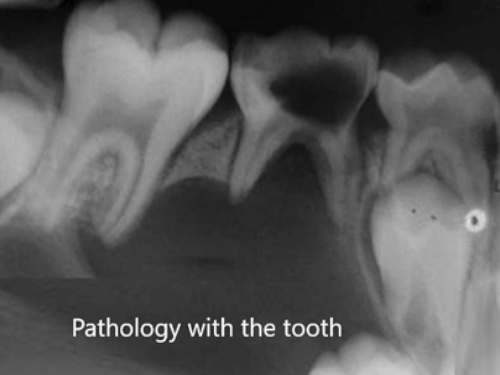

Any pathology associated with the tooth which is seen on Xray

The impacted that is not fully erupted third molars have to be extracted surgically. Under local anesthesia the bone and the soft tissue that is hindering its eruption are removed and then extraction is carried out followed by sutures